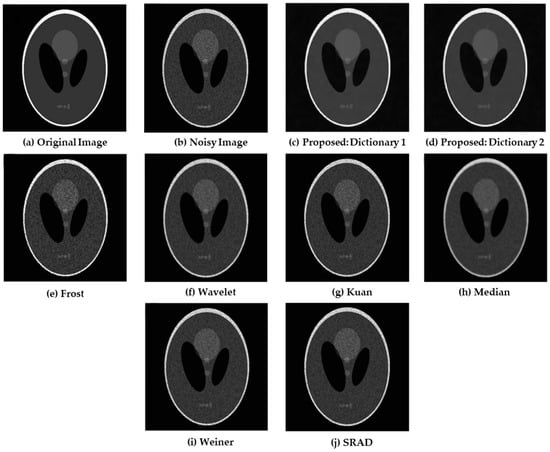

4.1. Simulations on Synthetic Images

| Models | PSNR (dB) | MSSIM |

|---|---|---|

| Frost | 28.966 | 0.822 |

| Median | 25.497 | 0.659 |

| Wavelet | 27.772 | 0.782 |

| SRAD | 28.766 | 0.813 |

| Kuan | 28.279 | 0.801 |

| Weiner | 29.218 | 0.834 |

| Proposed: Dictionary 1 | 30.334 | 0.901 |

| Proposed: Dictionary 2 | 30.807 | 0.926 |